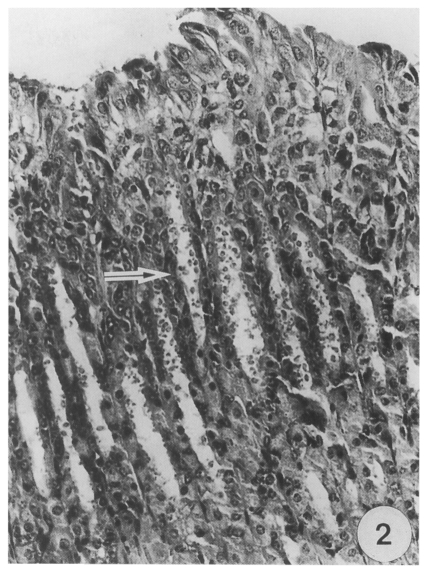

Structure of developmental stages

On light microscopy, Cryptosporidia were seen in the abomasal peptic glands of an infected kid. Most glands were found infected, and various developmental stages were observed from the apex to the orifice of the glands (Fig. 2). Under transmission electron microscopy, all developmental stages in the parasitophorous vacuoles (PV) were found in the pits of the gastric glands. The endogenous development of the parasite occurred in the microvilli of the surface mucus cells of the gastric glands. A projection of the parasite, which was called a "knob like projection" by Tyzzer (1910), was seen at the attachment site to the host cells. The outer aspect of the projection was surrounded by a thick, filamentous process of the host cell.

Fig. 2

Most abomasal peptic glands (arrow) of an infected kid are filled with large numbers of various Cryptosporidial forms, × 350, HE.

Fig. 2 Most abomasal peptic glands (arrow) of an infected kid are filled with large numbers of various Cryptosporidial forms, × 350, HE.